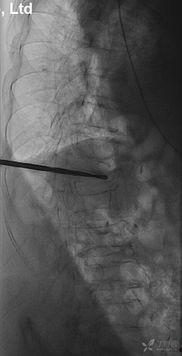

2. 穿刺:医生会在你的背部皮肤上打一个小孔,插入一根细长的穿刺针。这就像是在城堡的墙壁上开一个小窗户。

3. 注入骨水泥:通过穿刺针,医生会将一种特殊的骨水泥注入到压缩的椎体中。这种骨水泥具有很高的强度,可以迅速凝固,为椎体提供支撑。